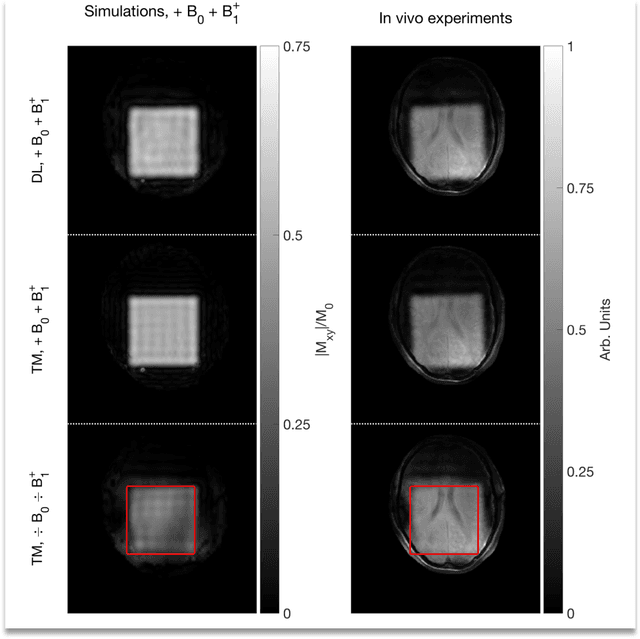

Abstract:Purpose: Rapid 2D RF pulse design with subject specific $B_1^+$ inhomogeneity and $B_0$ off-resonance compensation at 7 T predicted from convolutional neural networks is presented. Methods: The convolution neural network was trained on half a million single-channel transmit, 2D RF pulses optimized with an optimal control method using artificial 2D targets, $B_1^+$ and $B_0$ maps. Predicted pulses were tested in a phantom and in vivo at 7 T with measured $B_1^+$ and $B_0$ maps from a high-resolution GRE sequence. Results: Pulse prediction by the trained convolutional neural network was done on the fly during the MR session in approximately 9 ms for multiple hand drawn ROIs and the measured $B_1^+$ and $B_0$ maps. Compensation of $B_1^+$ inhomogeneity and $B_0$ off-resonances has been confirmed in the phantom and in vivo experiments. The reconstructed image data agrees well with the simulations using the acquired $B_1^+$ and $B_0$ maps and the 2D RF pulse predicted by the convolutional neural networks is as good as the conventional RF pulse obtained by optimal control. Conclusion: The proposed convolutional neural network based 2D RF pulse design method predicts 2D RF pulses with an excellent excitation pattern and compensated $B_1^+$ and $B_0$ variations at 7 T. The rapid 2D RF pulse prediction (9 ms) enables subject-specific high-quality 2D RF pulses without the need to run lengthy optimizations.